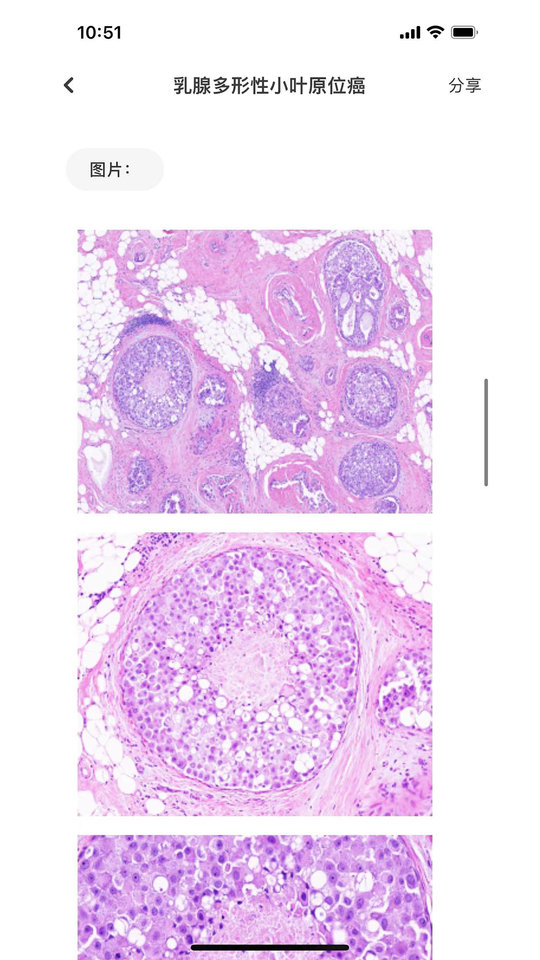

2、查阅诊断要点栏目获取各类疾病的典型临床表现与鉴别诊断标准,包含详细的症状描述与检查指标解读。

3、浏览免疫表型数据库了解不同细胞类型的表面标志物特征,支持通过分子标记组合进行精准分型查询。

全面专业的病理知识库:

2200+ 病理诊断与鉴别诊断知识库、400+ 免疫组化抗体应用介绍、800+ 肿瘤免疫表型介绍等

可以输入肿瘤名称、抗体名称、免疫组化染色项目、疾病名称、发病部位、形态结构、所属类别中任意内容进行综合查询,